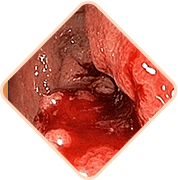

3 peligros mortales de hemorroides si no se trata a tiempo

Cualquiera de los siguientes puede ser

la causa de la muerte súbita del paciente!

Las heces contienen una cantidad gigantesca de gérmenes, bacterias y hongos. Si la infección ingresa al tejido pélvico y a los órganos vecinos, es posibleuna inflamación peligrosa y una infección de la sangre

Los vasos llenos del bulto hemorroidal son muy débiles. A menudo se rompen. El grado de pérdida de sangre en este caso puede ser tal que sea necesario transfusión de sangre

Se forman coágulos de sangre en los vasos. Estos coágulos de sangre pueden desprenderse y obstruir los vasos de los órganos internos, interrumpir la circulación sanguínea y causar un bloqueo en las arterias pulmonares.La probabilidad de muerte es alta.

No pongas tu vida en peligro.

Utiliza in nuevo

remedio certificado - Relifix